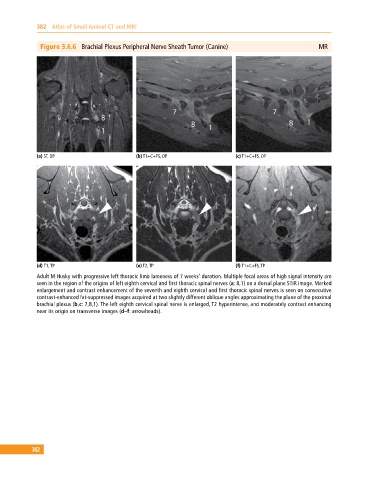

Figure 3.6.6 Brachial Plexus Peripheral Nerve Sheath Tumor (Canine) MR

(a) ST, DP (b) T1+C+FS, OP (c) T1+C+FS, OP

(d) T1, TP (e) T2, TP (f) T1+C+FS, TP

Adult M Husky with progressive left thoracic limb lameness of 7 weeks’ duration. Multiple focal areas of high signal intensity are

seen in the region of the origins of left eighth cervical and first thoracic spinal nerves (a: 8,1) on a dorsal plane STIR image. Marked

enlargement and contrast enhancement of the seventh and eighth cervical and first thoracic spinal nerves is seen on consecutive

contrast‐enhanced fat‐suppressed images acquired at two slightly different oblique angles approximating the plane of the proximal

brachial plexus (b,c: 7,8,1). The left eighth cervical spinal nerve is enlarged, T2 hyperintense, and moderately contrast enhancing

near its origin on transverse images (d–f: arrowheads).